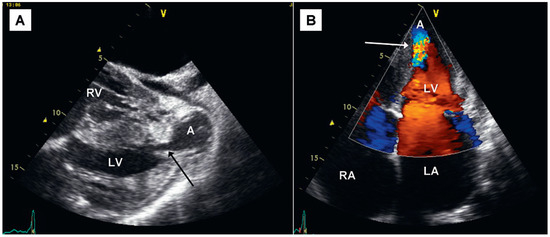

Giant Apical Aneurysm without Coronary Artery Disease

by Stéphane Chevallier and Jean-Christophe Stauffer

A 66-year-old patient with some years’ history of apical hypertrophic cardiomyopathy treated by beta-blockers attended for follow-up echocardiography [...] Full article